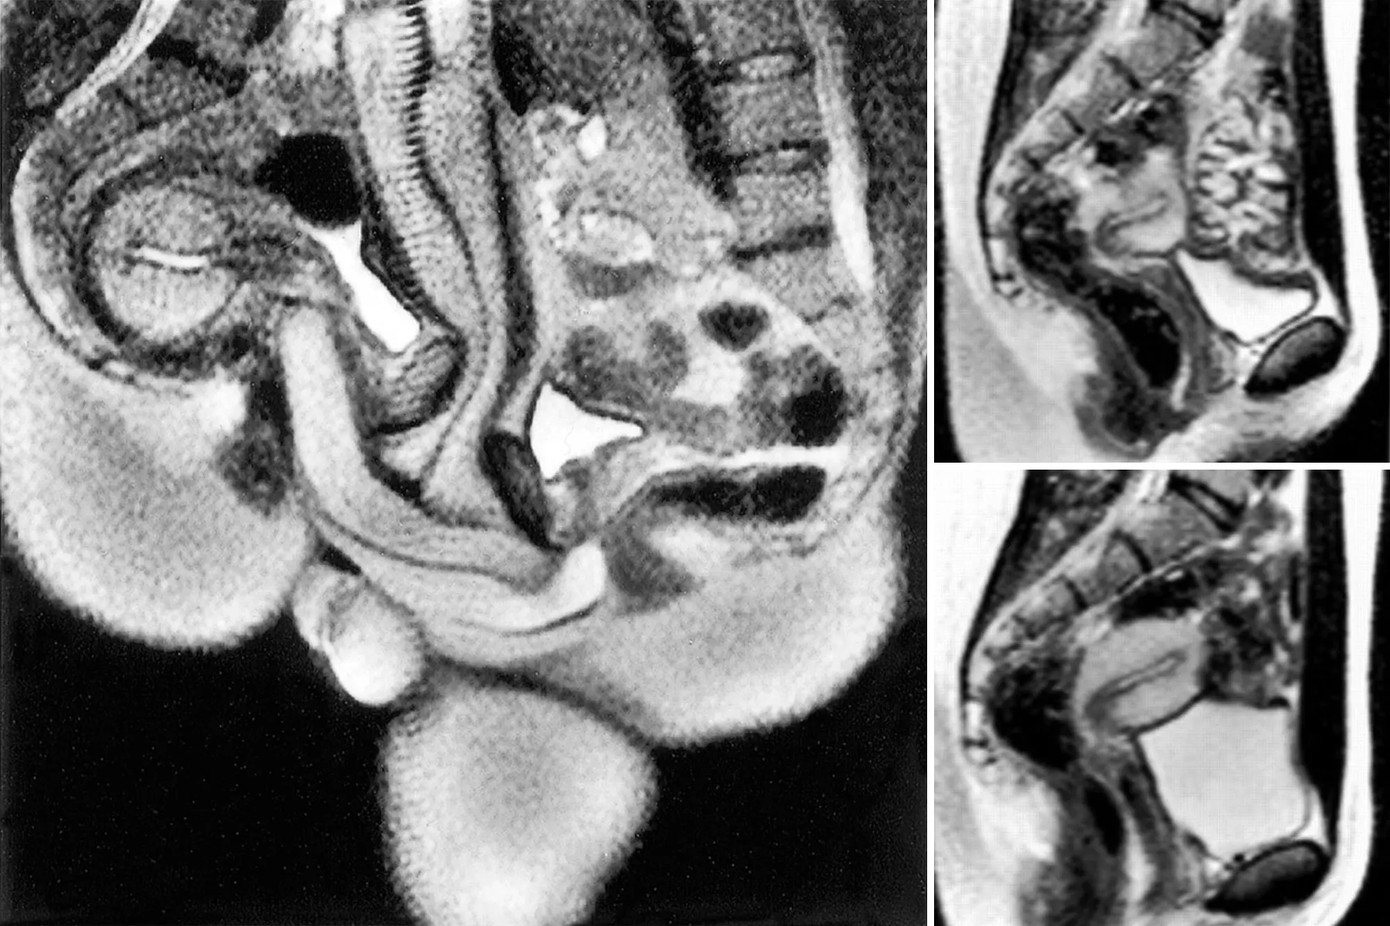

Một trong những phát hiện đáng chú ý nhất từ thí nghiệm này là âm đạo của phụ nữ không chỉ đơn giản là một đường hầm thẳng. Từ lâu người ta vẫn tin rằng “cậu nhỏ” đi thẳng vào, giống như những mô tả trong bức họa nổi tiếng của Leonardo da Vinci từ năm 1492.

| "Cậu nhỏ" có hình dạng của một chiếc boomerang khi ái ân. |

Thế nhưng, kết quả chụp cộng hưởng từ cho thấy “cậu nhỏ” có hình dạng của một chiếc boomerang, nghĩa là nó uốn cong vào bên trong theo hình dạng của cơ thể phụ nữ mà không gây đau đớn cho người đàn ông khi cương cứng.